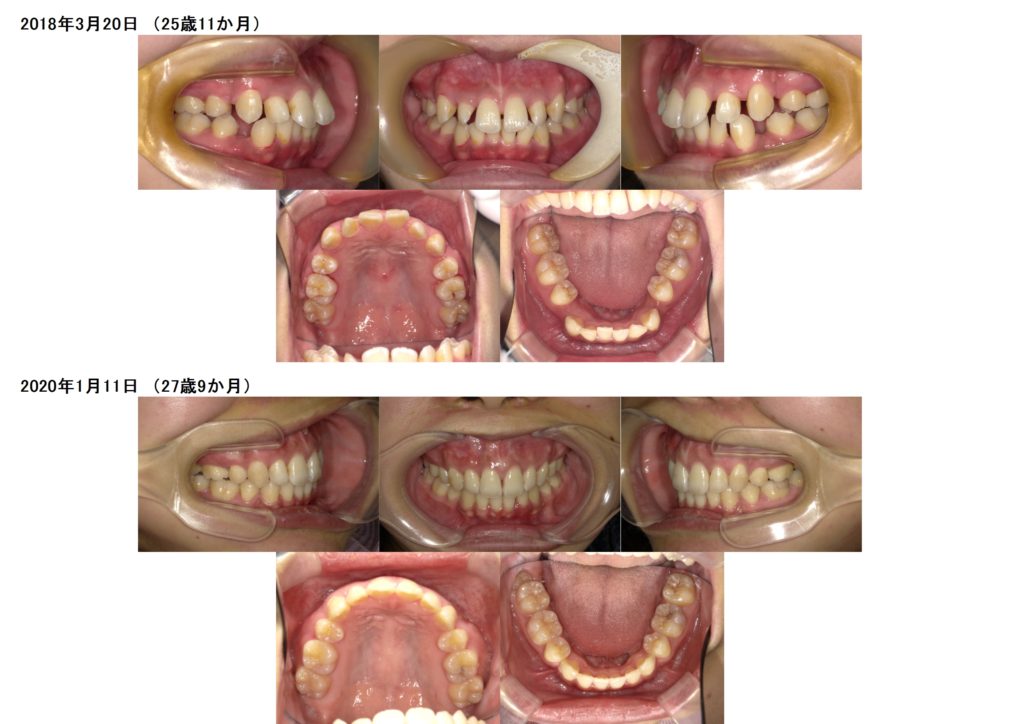

↑治療前、治療後の口腔内写真の比較です。

お口元の突出や、ガミースマイルを気にされての来院でしたが、とてもきれいに引っ込み、歯並び、噛み合わせ、横顔のラインも美しく完了しました。